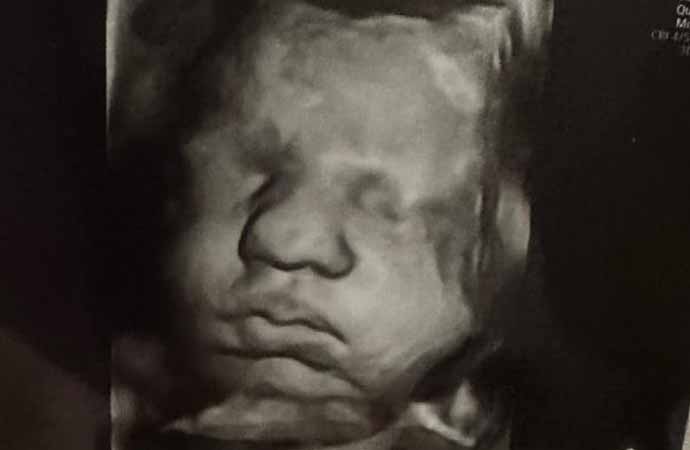

Hatcher'ın doktoru, genç kadının iki rahminde iki ayrı bebeğe aynı anda hamile kalmasının milyonda bir olduğunu söyledi.